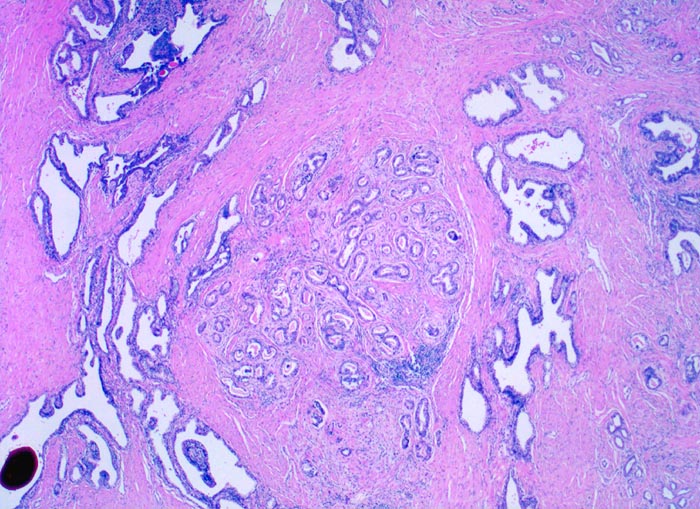

PathoPic – image database / PathoPic ID 4622 - Adenokarzinom der Prostata

Adenokarzinom der Prostata

Neben grossen normalen Prostatadrüsen mit grossen Lumina ist in der Übersicht ein gut umschriebener Herd dicht gelagerter mittelgrosser gut geformter Drüsen mit intraluminalem Sekret erkennbar. Innerhalb dieses Karzinomherdes sind keine normalen Drüsen erkennbar. Das Karzinom infiltriert also nicht das Normalgewebe. Dieser Tumorherd entspricht einem Gleason Grad 2.

Eingedicktes Sekret mit Ausbildung eines Corpus amylaceum in einer benignen Drüse.

Die Diagnose eines Prostatakarzinoms lässt sich bereits in der Übersichtsvergrösserung aufgrund der Ansammlung kleiner Drüsen stellen. Ein umschriebenes noduläres Infiltrat grösserer gut geformter Karzinomdrüsen, welches das normale Prostatagewebe intakt lässt, entspricht einem Gleason Grad 2.

Der histologische Grad eines Prostatakarzinoms korreliert mit dem Progressionsrisiko. Das Grading nach Gleason umfasst einen Wert zwischen 1 (gut differenziert) und 5 (wenig differenziert) und berücksichtigt die Architektur der Karzinomdrüsen. Prostatakarzinome sind oft heterogen bezüglich Differenzierung. Der Gleason Score wird ausgedrückt als Summe der beiden prädominanten Wachstumsmuster. Das häufigere Muster wird dabei zuerst genannt. Ein Gleason Score: 4+3=7 bedeutet, dass das Wachstumsmuster entsprechend einem Gleason Grad 4 dominiert. Bei einem Tumor, der zu mehr als 95% ein einheitliches Wachstumsmuster zeigt wird der entsprechende Gleason Grad zweimal gezählt. Bsp. 3+3=6.

Tumoren mit einem Gleason Score bis 6 sind hoch differenziert, mit einem Gleason Score 7 bis 8 mässig und einem Gleason Score 9 bis 10 schlecht differenziert.